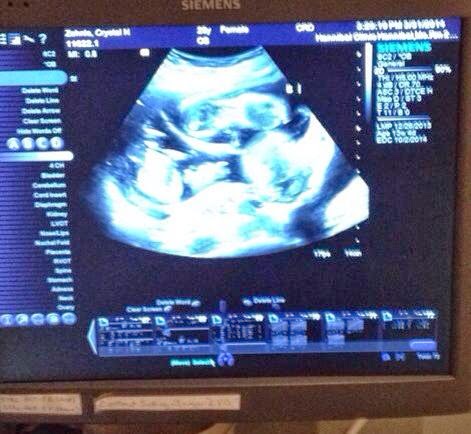

We had our second appointment and ultrasound yesterday and it was a complete turn around from the first appointment! I walked in so excited to see our babies! We started with an ultrasound so that they could measure the babies and check for placentas and sacs. Good news! Each baby has their own sac and their own placenta. This brings the risk factor way down, because each baby has their own source of nourishment and blood flow. This was great news!

Each baby is approximately 8 cm long and their heartbeats measured the same! We were just in awe of how much they have progressed from 10 weeks to 14 weeks! It's just amazing! They looked perfect and we couldn't be more thrilled! They couldn't print out pictures for this ultrasound, but we did take some on our phones.